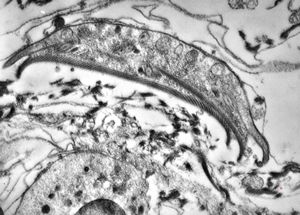

Giardia (Lamblia) intestinalis